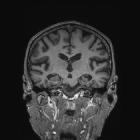

MRI

The primary role of MRI (and CT for that matter) in the diagnosis of Alzheimer disease is the assessment of volume change in characteristic locations which can yield a diagnostic accuracy of up to 87% . Unfortunately, such volume loss is not apparent early in the course of the disease .

Mesial temporal lobe atrophy can be assessed directly or indirectly. Direct assessment is of hippocampal or parahippocampal volume loss while indirect assessment relies on an enlargement of the parahippocampal fissures. The former is more sensitive and specific but ideally, requires actual volumetric calculations rather than 'eyeballing' the scan . These measures have been combined in the medial temporal atrophy score which has been shown to be predictive of progression from mild cognitive impairment (MCI) to dementia .

Additionally, and particularly relevant to posterior cortical atrophy or early-onset Alzheimer disease, is the presence of parietal atrophy. This is often best seen on the interhemispheric surface of the parietal lobe (see neurodegenerative MRI brain: an approach) by examining the posterior cingulate sulcal and parieto-occipital sulcal size and degree of atrophy of the precuneus and cortical surface of the parietal lobe. This has also been combined into a scoring system (see posterior atrophy score of parietal atrophy a.k.a. Koedam score).